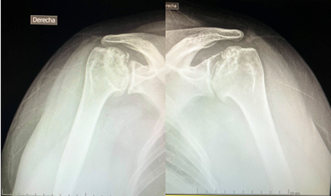

En las radiografías de hombro observamos gran fragmentación de ambas epífisis con pérdida de la morfología normal y cambios degenerativos secundarios. Figura 2